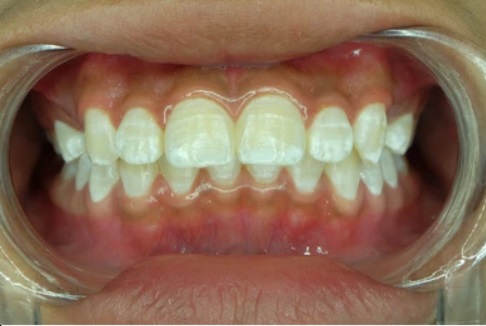

Dental fluorosis occurs when excessive fluoride is absorbed during tooth development, resulting in changes in the appearance of the tooth enamel. While fluoride is essential for healthy teeth, overexposure to fluoride can lead to unsightly white spots, streaks, or even brown stains on the teeth.

Fluorosis can vary in severity, ranging from mild to severe, and its impact on the aesthetics and overall health of your smile can differ accordingly. It is important to understand the causes and symptoms of dental fluorosis to prevent and address this condition effectively.

The symptoms and signs of dental fluorosis can vary depending on the severity of the condition. In mild cases, there may be barely noticeable white streaks or spots on the enamel. However, as the severity increases, the appearance of the teeth can be significantly affected.

Moderate to severe fluorosis can lead to brown stains, pitting, or cracking of the enamel, making the teeth more susceptible to tooth decay and sensitivity. It is important to be aware of these symptoms and consult with a dental professional for an accurate diagnosis and appropriate treatment.